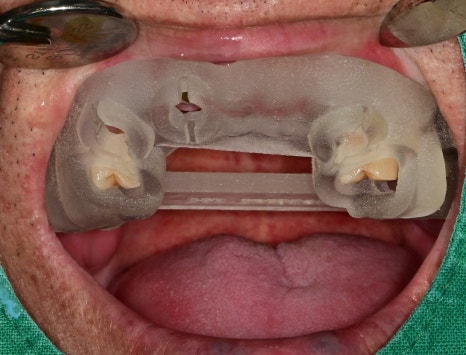

또한, 잇몸을 열지 않고 수술하는 것이 훨씬 유리했기에

가이드를 이용하여 식립 경로를 다시 한번 확실하게 시립이 가능했습니다.

발치가 된 빈 공간에 추가적인 치조골이식술을 시행한 후

동시에 적합한 직경의 임플란트를 식립했습니다

수술 후의 사진입니다.